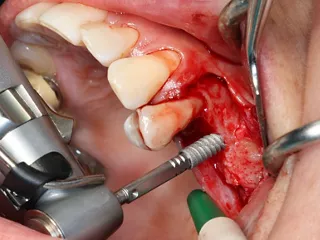

5. A full-thickness flap was elevated and a releasing incision made mesial to 24. Care must be taken at this stage not to damage the periosteum.

6. A lateral sinus lift was performed by creating a 7 × 5 mm window using a round tungsten carbide bur followed by a diamond bur.